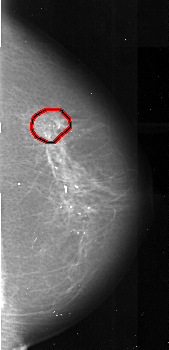

A_1021_1.LEFT_MLO

FILE: A_1021_1.RIGHT_MLO.OVERLAY

TOTAL_ABNORMALITIES 1

ABNORMALITY 1

LESION_TYPE MASS SHAPE ARCHITECTURAL_DISTORTION MARGINS SPICULATED

ASSESSMENT 4

SUBTLETY 3

PATHOLOGY MALIGNANT

TOTAL_OUTLINES 1

BOUNDARY